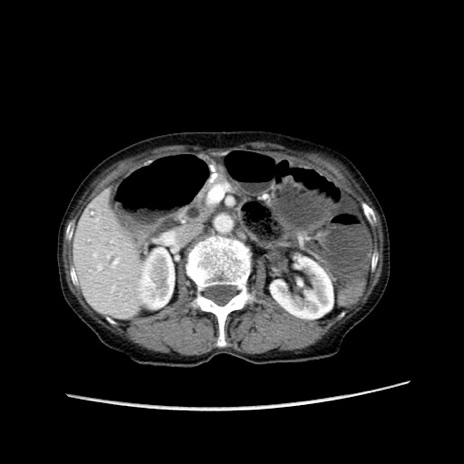

症例25(横断像)

【症例】80歳代女性

【主訴】胸のつかえ感

【現病歴】約9時間前に食後から胸のつかえた感じあり、嘔吐あり、来院。

【既往歴】胃癌(全摘)、胆摘、虫垂炎

【身体所見】心窩部に圧痛あり、反跳痛なし。

【データ】WBC 5700、CRP 0.05